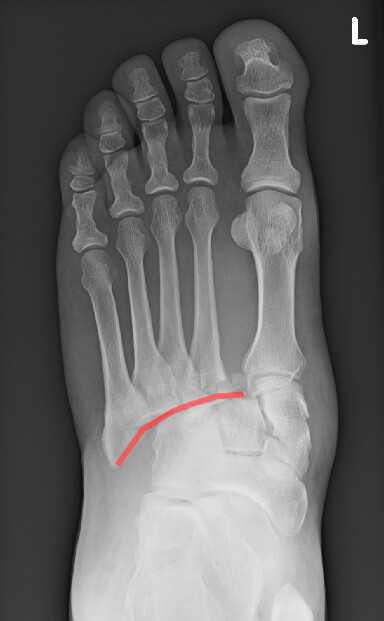

James Heilman, MD - File:LisFranc.png, CC BY-SA 4.0, Link

L’articulation de Lisfranc unit le tarse antérieur (les 3 cunéiformes et le cuboïde) aux métatarsiens.

Signes radiologiques : perte des repères anatomiques normaux :

- De face : le bord de M2 doit être aligné avec le bord du 2° cunéiforme